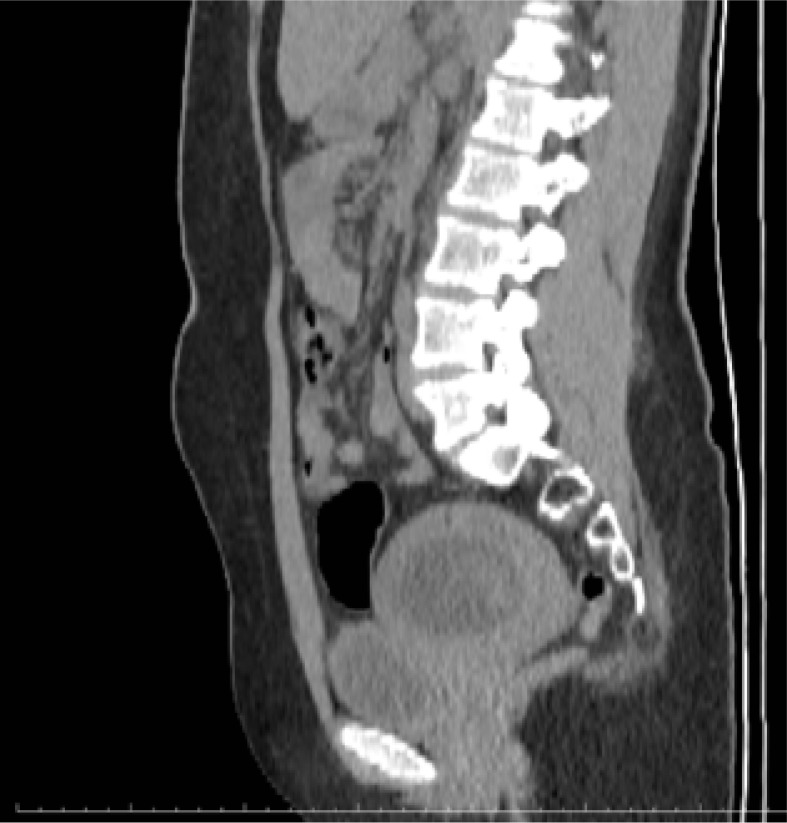

Should routine β-hCG testing be performed before computed tomography scans in women of childbearing age?

育龄妇女应在计算机断层扫描前进行β-hCG常规检测吗?